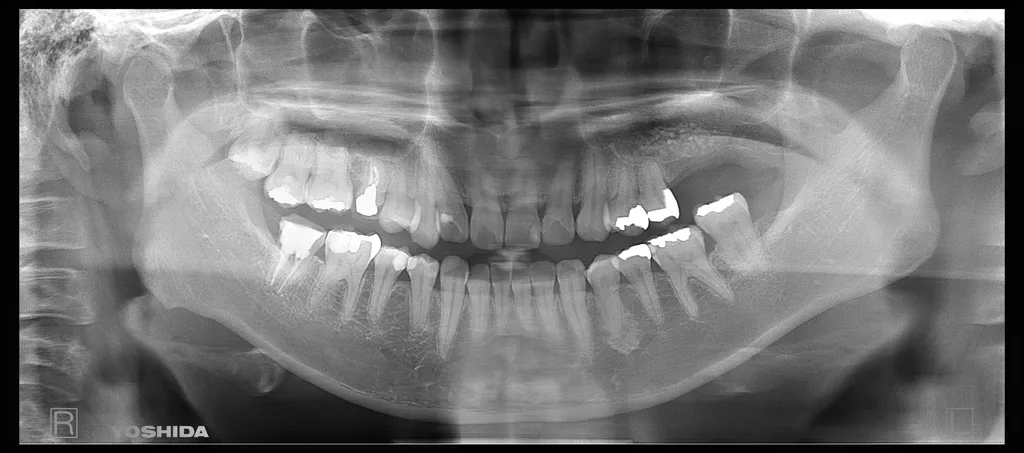

インプラントの症例

33歳女性

左上を抜いて10年以上経っている。インプラントをしたい。

治療部位:26,27

治療方法:サイナスリフト6ヶ月待機+通常待機埋入

種類:ITI(ストローマン)+ジルコニア